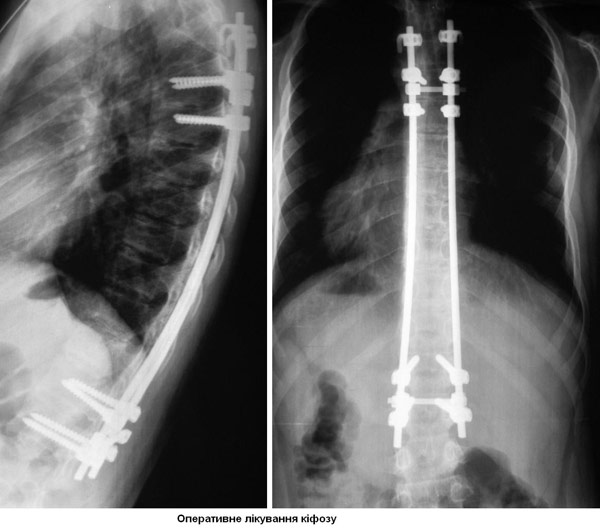

Операція

Операція полягає в імплантації в хребет металевої конструкції (гвинтів, гачків), які дозволяють вирівнювати хребет на спеціальних стрижнях. Після операції не використовуються корсети, гіпс і т.п.

Термін госпіталізації при одній операції близько 10 днів. Такі операції також показані і при сколіозах, посттравматичних і післяопераційних викривленнях хребта. Непроопероване викривлення хребта супроводжується дихальною недостатністю, зміщенням внутрішніх органів, проблемами при вагітності.

Стандартним класичним оперативним втручанням при кіфозі і сколіозі вважається операція французьких хірургів Котреля і Дюбуссе. Вказана методика була вперше в Україні застосовано нами ще в 1999 році. Зараз у Міжнародному центрі нейрохірургії впроваджена новітня, більш ефективна модифікація цих операцій, розроблена корейським хірургом Суком і американським Ленке. Перші такі операції виконані нами в грудні 2006 року. Міжнародний центр нейрохірургії користується імпортними конструкціями американського виробництва, які вважаються кращими в світі (системи CD HORIZON (M 10, M8), LEGACY - (Medtronic) США).